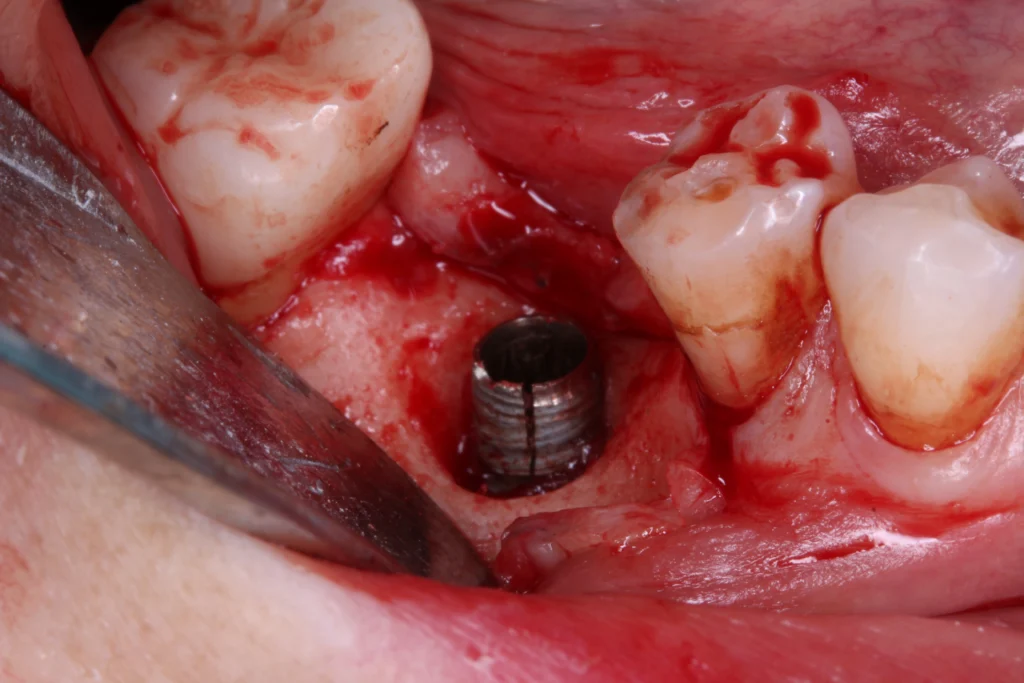

- Implant Removal & Replacement – In severe cases, we carefully remove the failing implant and rebuild the site with grafting before placing a new one.